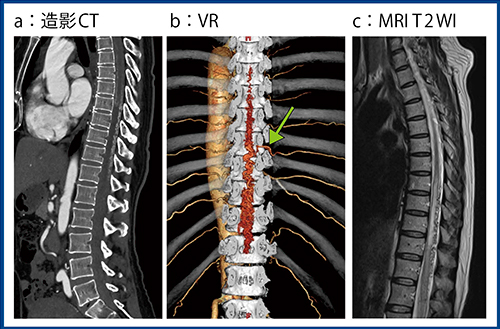

症例5(図5)は50歳代,男性,脊髄硬膜動静脈瘻で,Aquilion PrecisionのSHRモードによる造影CT(a)とVR画像(b)にて非常に拡張した静脈瘻とそのfeeder(←)および別のレベルより起始するAdamkiewicz動脈が確認された。MRIのT2強調画像(図5 c)では,胸随から腰随にかけて高信号を伴い,背側側に無信号域(flow void)を認めた。脊髄硬膜動静脈瘻のfeederに対して液体塞栓物質を用いて塞栓術を施行したところ,flow voidが消失し,脊椎の浮腫も改善した。

図5 症例5:脊髄硬膜動静脈瘻における血管塞栓術術前の評価